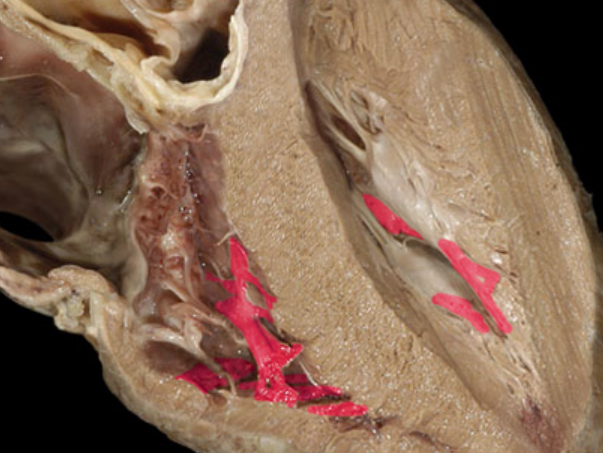

What is this structure and which kinds of valves possess them?

A

Chordae Tendineae of Valve

Atrioventricular Valves (Tricuspid and Bicuspid valves)